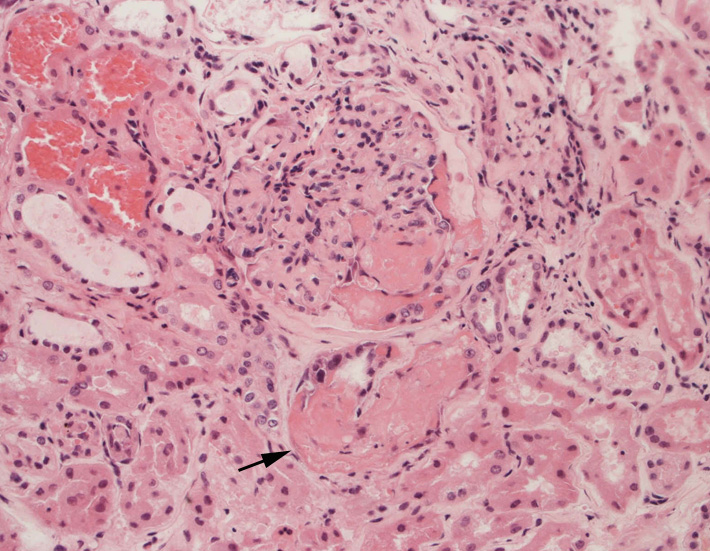

腎臓の病理組織所見-->壊死性糸球体腎炎

Fig.01Fig.02Fig.03

Fig.03(PAS)Fig.04(PAM染色)Fig.05(PAM染色)

Fig.06Fig.07 尿細管壊死